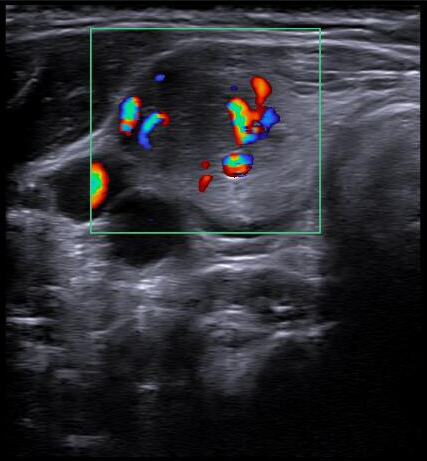

Ecografía tiroidea en AP: En lóbulo tiroideo derecho se aprecia nódulo: hipoecogénico, sólido, con márgenes definidos, sin focos ecogénicos, que presenta vascularización periférica, de morfología ovoide y de dimensiones 32x17x19 mm aproximadamente (CCxAPxT, más alto que ancho). Compatible con TIRADS 4.